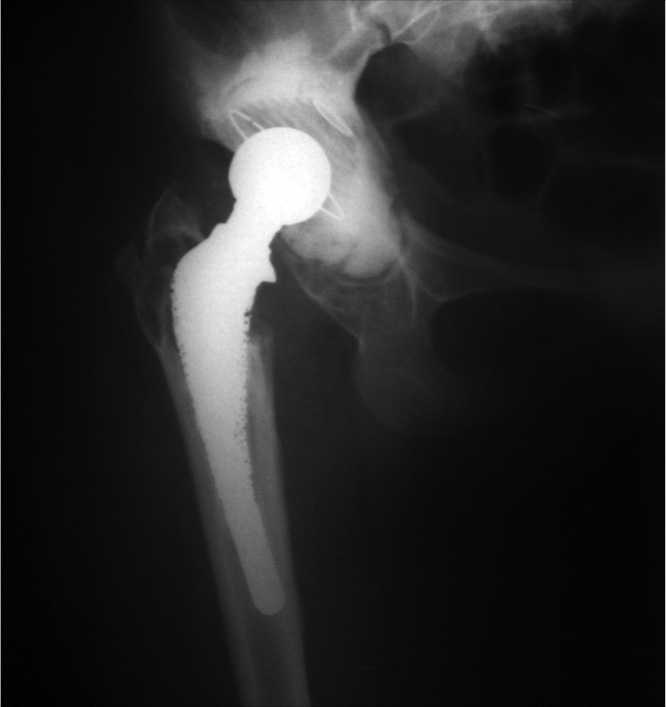

Операцию выполняли в положении больной лежа на здоровом боку с использованием прямого бокового доступа. Удалили рубцово-измененные ткани. При удалении бедренного компонента произошел перелом бедренной кости. Вертлужный компонент с остатками костного цемента удалили без технических трудностей. Выполнили анатомическую установку индивидуальной 3D-конструкции согласно предоперационному планированию и фиксацию 7 винтами.

В полусферическую часть 3D-имплантата установили ацетабулярный компонент цементной фиксации двойной мобильности Novae Stick 45 мм. Проксимальный фрагмент бедренной кости, сломанный при удалении бедренного компонента, фиксировали 5 серкляжными швами и в бедренную кость имплантировали ревизионный бедренный компонент Wagner SL 190/14 (рис. 14).

Рис. 14. Рентгенограмма после операции: достигнута прочная первичная фиксация имплантата в кости, восстановлено анатомическое положение вертлужной впадины

Длительность операции составила 190 мин, кровопотеря — 1500 мл. Продолжительность нахождения пациентки в отделении реанимации — 1 сут. Общая продолжительность стационарного лечения — 14 дней. Послеоперационная рана зажила первичным натяжением. Септических осложнений, вывихов и миграции имплантатов в раннем послеоперационном периоде не было.